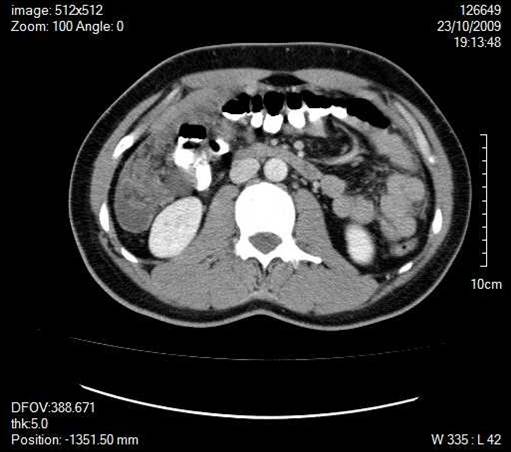

A 30-year old man presented with symptoms and signs of acute appendicitis. Abdominal imaging via ultrasound and computed tomography detected a mass in the right iliac fossa. Exploratory laparotomy revealed an appendiceal mass and gelatinous peritoneal fluid, while histopathology confirmed the diagnosis of pseudomyxoma peritonei arising from a mucocele of the appendix and attributed to an appendiceal cystadenocarcinoma. The clinical and imaging findings of this rare case are herein presented.